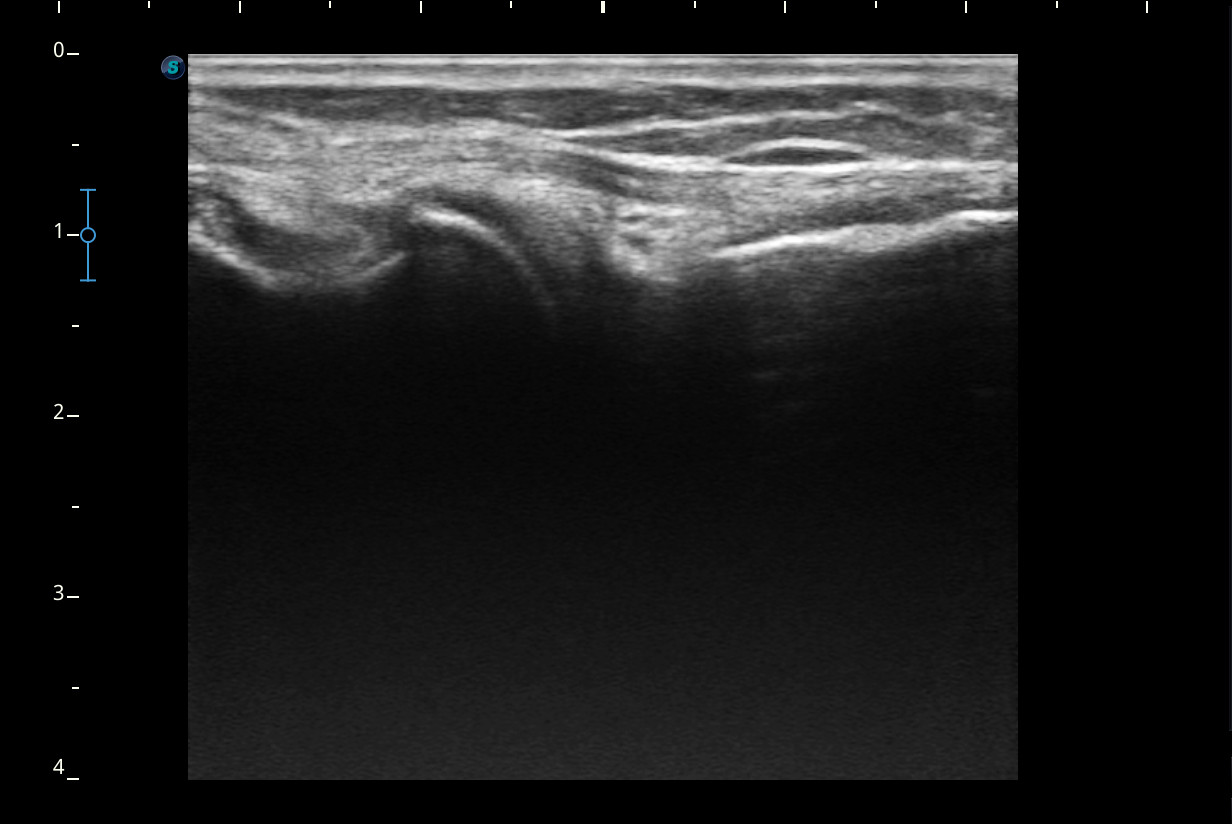

Rodilla sin derrame articular. No se aprecian lesiones en Ligamentos colaterales. Ligamento rotuliano sin hallazgos valorables. Rotura menisco interno y dudosa fisura menisco externo. Tendones rotuliano y cuadricipital normales.

Resonancia magnética confirma rotura cuerno posterior menisco interno.

Rotura cuerno posterior menisco interno.